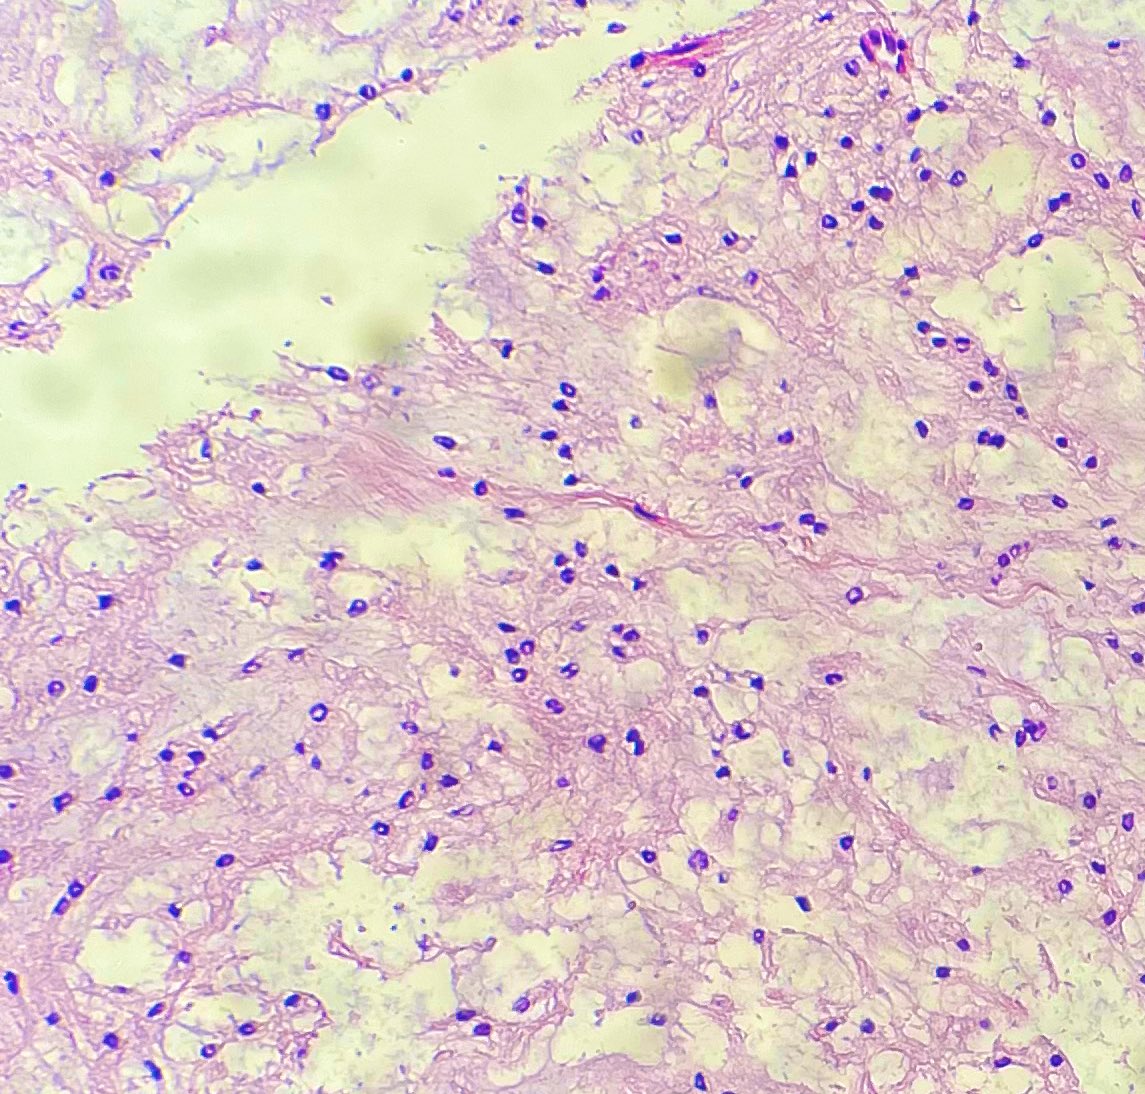

Ulcerated Anal Amelanotic Melanoma in 60y/M. #APCON2022 #APCON2022PathTweet GI James Padma Priya J Kenny De Gracia T. Archana bhat Aditya Agnihotri 🇮🇳 Vijay Shankar S Annie A. Wu, MD, PhD Olaleke Folaranmi Daisy Maharjan Dante Aswathy Menon Ananthvikas Dr Anila Sharma Frank Ingram, MD Arunima Deb, MD #pathology #PathTwitter

Gross Spotter craze- Adrenal myelolipoma, admixture of adipose tissue and haemorrhagic areas. #APCON2022 #APCON2022PathTweet Adriana Ancer Padma Priya J Aditya Agnihotri 🇮🇳 Archana bhat Annie A. Wu, MD, PhD Frank Ingram, MD Daisy Maharjan Sandeep Mathur Department of Pathology, AIIMS, New Delhi Dr Anila Sharma Arunima Deb, MD

1 slide diagnosis #PathTwitter #pathboards Swathi Prabhu, MD Padma Priya J Carlos Miguel Ruiz Arunima Deb, MD